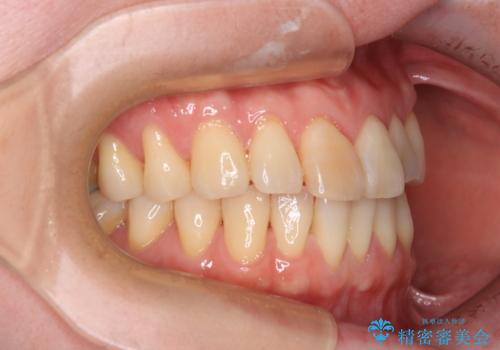

前歯のデコボコをインビザライン・モデレートで矯正治療

- 上下前歯のデコボコを気にして来院された患者様です。

安価なインビザラインパッケージを用いての治療を希望されており、デコボコの程度が中等度であったため、インビザライン・モデレートを用いて矯正治療を行うこととしました。

インビザライン・モデレートは、製作できるアライナーの枚数に制限があるため、移動可能な量に限りがあるものの、インビザライン・ライトよりも枚数が多いため、幅広い症例に対応可能です。